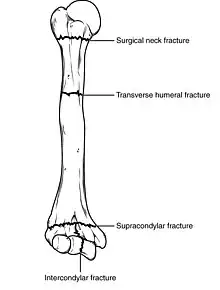

| Humerus fracture | |

Fractures of the humerus are classified based on the location of the fracture and then by the type of fracture. There are three locations that humerus fractures occur: at the proximal location, which is the top of the humerus near the shoulder, in the middle, which is at the shaft of the humerus, and the distal location, which is the bottom of the humerus near the elbow.[9] Proximal fractures are classified into one of four types of fractures based on the displacement of the greater tubercle, the lesser tubercle, the surgical neck, and the anatomical neck, which are the four parts of the proximal humerus, with fracture displacement being defined as at least one centimeter of separation or an angulation greater than 45 degrees. One-part fractures involve no displacement of any parts of the humerus, two-part fractures have one part displaced relative to the other three; three-part fractures have two displaced fragments, and four-part fractures have all fragments displaced from each other.[13][14][3] Fractures of the humerus shaft are subdivided into transverse fractures, spiral fractures, "butterfly" fractures, which are a combination of transverse and spiral fractures, and pathological fractures, which are fractures caused by medical conditions.[12] Distal fractures are split between supracondylar fractures, which are transverse fractures above the two condyles at the bottom of the humerus, and intercondylar fractures, which involve a T- or Y-shaped fracture that splits the condyles.[7]